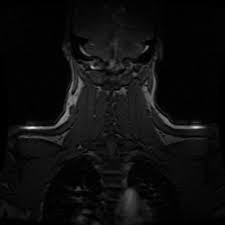

Ich weiß natürlich nicht wie es bei dir ist. Ich war eigentlich aus einem ganz anderen orthopädischen Grund in der Röhre Was könnte das sein. Je nach Ausmaß der Rückenschmerzen werden von der Halswirbelsäule HWS der Brustwirbelsäule BWS oder der Lendenwirbelsäule LWS durch Optimierungsprozesse der jeweiligen Untersuchung hochauflösende und dünnschichtige Bilder in Top-Qualität erstellt.